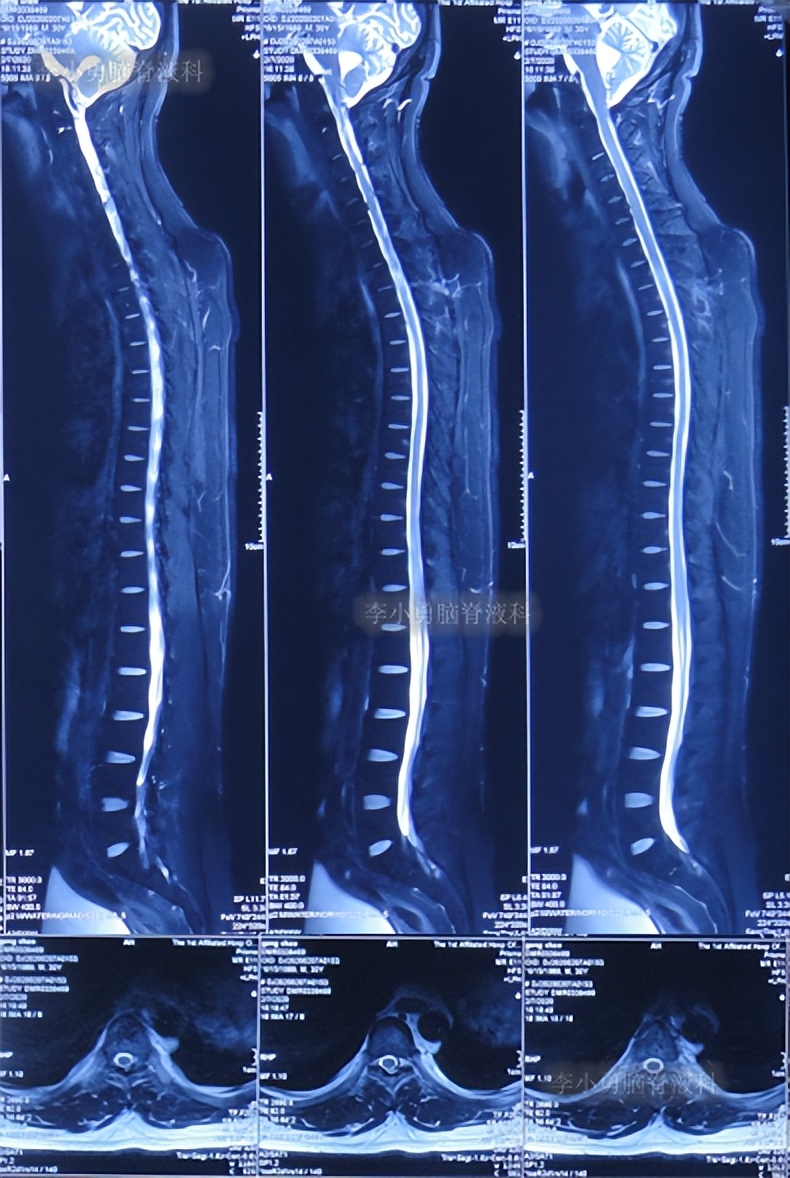

第2次的左侧脑室腹腔分流术后38天即2020年2月7日,查脊髓核磁示未见明显异常(图-9)。

图-9:2020年2月7日脊髓核磁